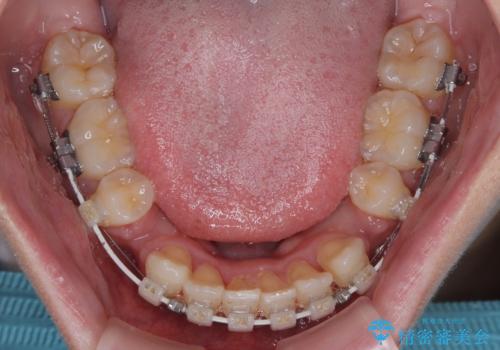

- 審美装置

- 1年10ヶ月

- 10-30回